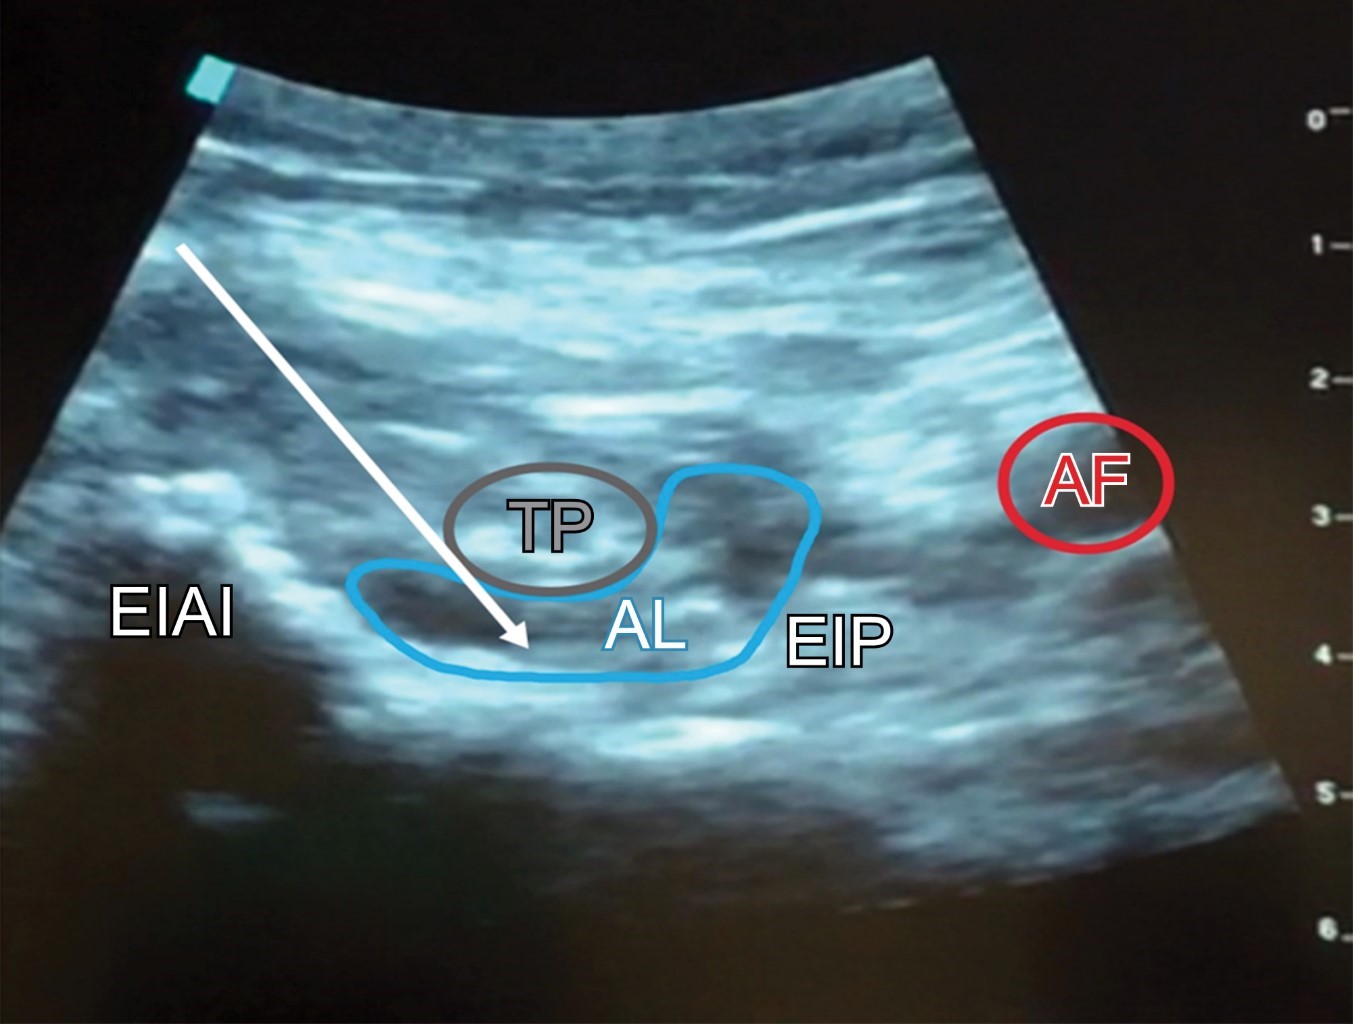

El bloqueo PENG se realizó según lo descrito por Arango y colaboradores.18 Con el paciente en decúbito supino, previa asepsia y antisepsia de la región inguinal, se coloca inicialmente un transductor de baja frecuencia (2-5 MHz) en un plano transversal sobre la espina iliaca anteroinferior (EIAI); posteriormente se alinea con la rama púbica, girando el transductor 45 grados en sentido medial. En esta posición, se identifica la eminencia iliopúbica (EIP), el músculo y tendón del psoas, la arteria femoral y el músculo pectíneo. Se inserta una aguja de 100 mm calibre 22 G, de lateral a medial en un abordaje en plano para colocar la punta en el plano musculofascial entre el tendón del psoas en la parte anterior y la rama púbica en la parte posterior. Después de la aspiración negativa, se inyecta la solución de anestésico local ropivacaína 0.375% en incrementos de 5 mL con un volumen total de 20 mL mientras se observa la adecuada dispersión de líquido en este plano (Figura 2).

Figura 2